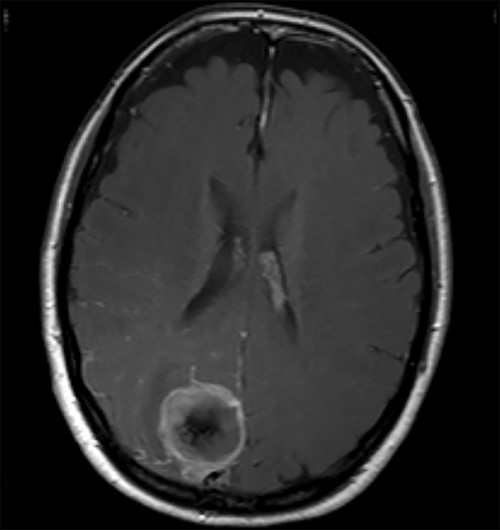

A 52-year-old female presented with headache and visual disturbance. She had no significant past medical history. On examination, a left homonomous inferior quadrantopia was noted. CT and then MRI imaging revealed a solitary 3-cm right parieto-occipital extra-axial lesion with associated dural tail and surrounding oedema (Fig. 1). Her headaches improved with a short course of steroids and the neuro-oncology MDT recommendation was for surgical excision of the suspected meningioma.

Axial view of a T1 weighted MRI post-gadolinium enhancement demonstrating the appearance of a 3-cm right parieto-occipital extra-axial mass with bony involvement and adjacent small nodule. Most in keeping with a meningioma.